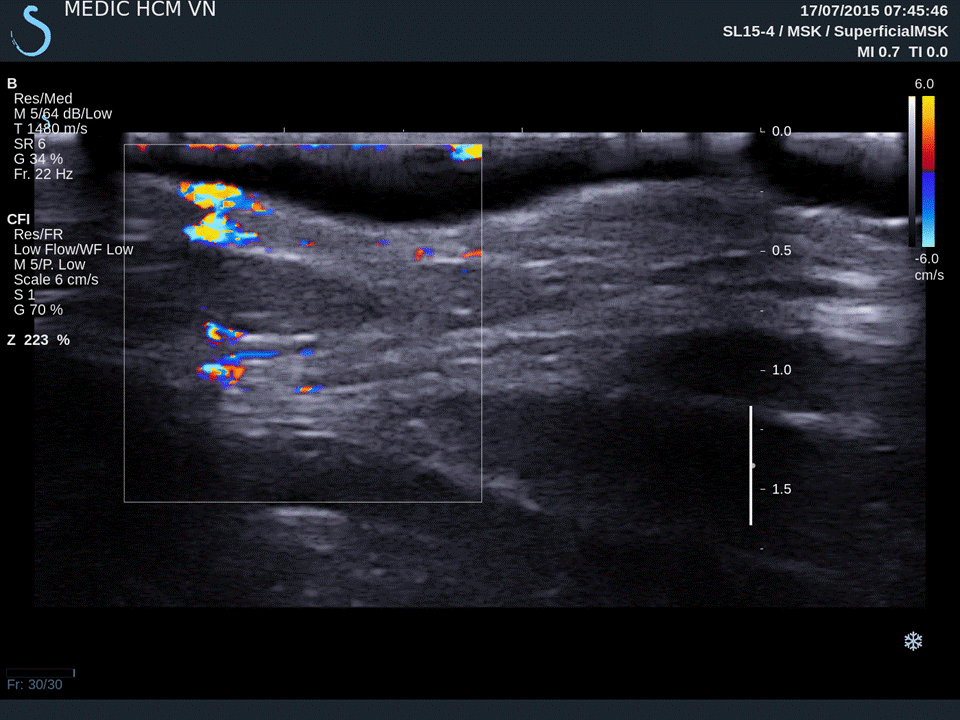

What Do The Red And Blue Marks Mean On An Ultrasound . On a normal ultrasound, however, the red and blue colors reflect the direction of blood flow to or away from the ultrasound. By evaluating these colors and grayscale imaging, clinicians can assess vascular conditions such as stenosis or thrombosis. Color & spectral doppler ultrasound interpretation |. Tips to read an ultrasound image. Red and blue colors represent the movement of the blood. Start from the top of the image and look for any differences in color. What do red and blue mean on an ultrasound? What does red or blue mean on an ultrasound? No, red and blue on an ultrasound do not mean cancer. The markings on an ultrasound that have a random string of letters and numbers are markings indicating the kind of ultrasound machine that was. What do red and blue colors mean? Solid tissue appears white because the outer surface reflects more sound,. For example, blue may indicate blood flowing away from the transducer (towards negative doppler shifts), while red represents blood moving towards the transducer (positive doppler shifts). In doppler ultrasounds, red and blue colors have specific meanings. These colors are solely indicators of blood flow direction and velocity,.

Start from the top of the image and look for any differences in color. For example, blue may indicate blood flowing away from the transducer (towards negative doppler shifts), while red represents blood moving towards the transducer (positive doppler shifts). Tips to read an ultrasound image. Color & spectral doppler ultrasound interpretation |. What does red or blue mean on an ultrasound? No, red and blue on an ultrasound do not mean cancer. These colors are solely indicators of blood flow direction and velocity,. On a normal ultrasound, however, the red and blue colors reflect the direction of blood flow to or away from the ultrasound. Red and blue colors represent the movement of the blood. By evaluating these colors and grayscale imaging, clinicians can assess vascular conditions such as stenosis or thrombosis.